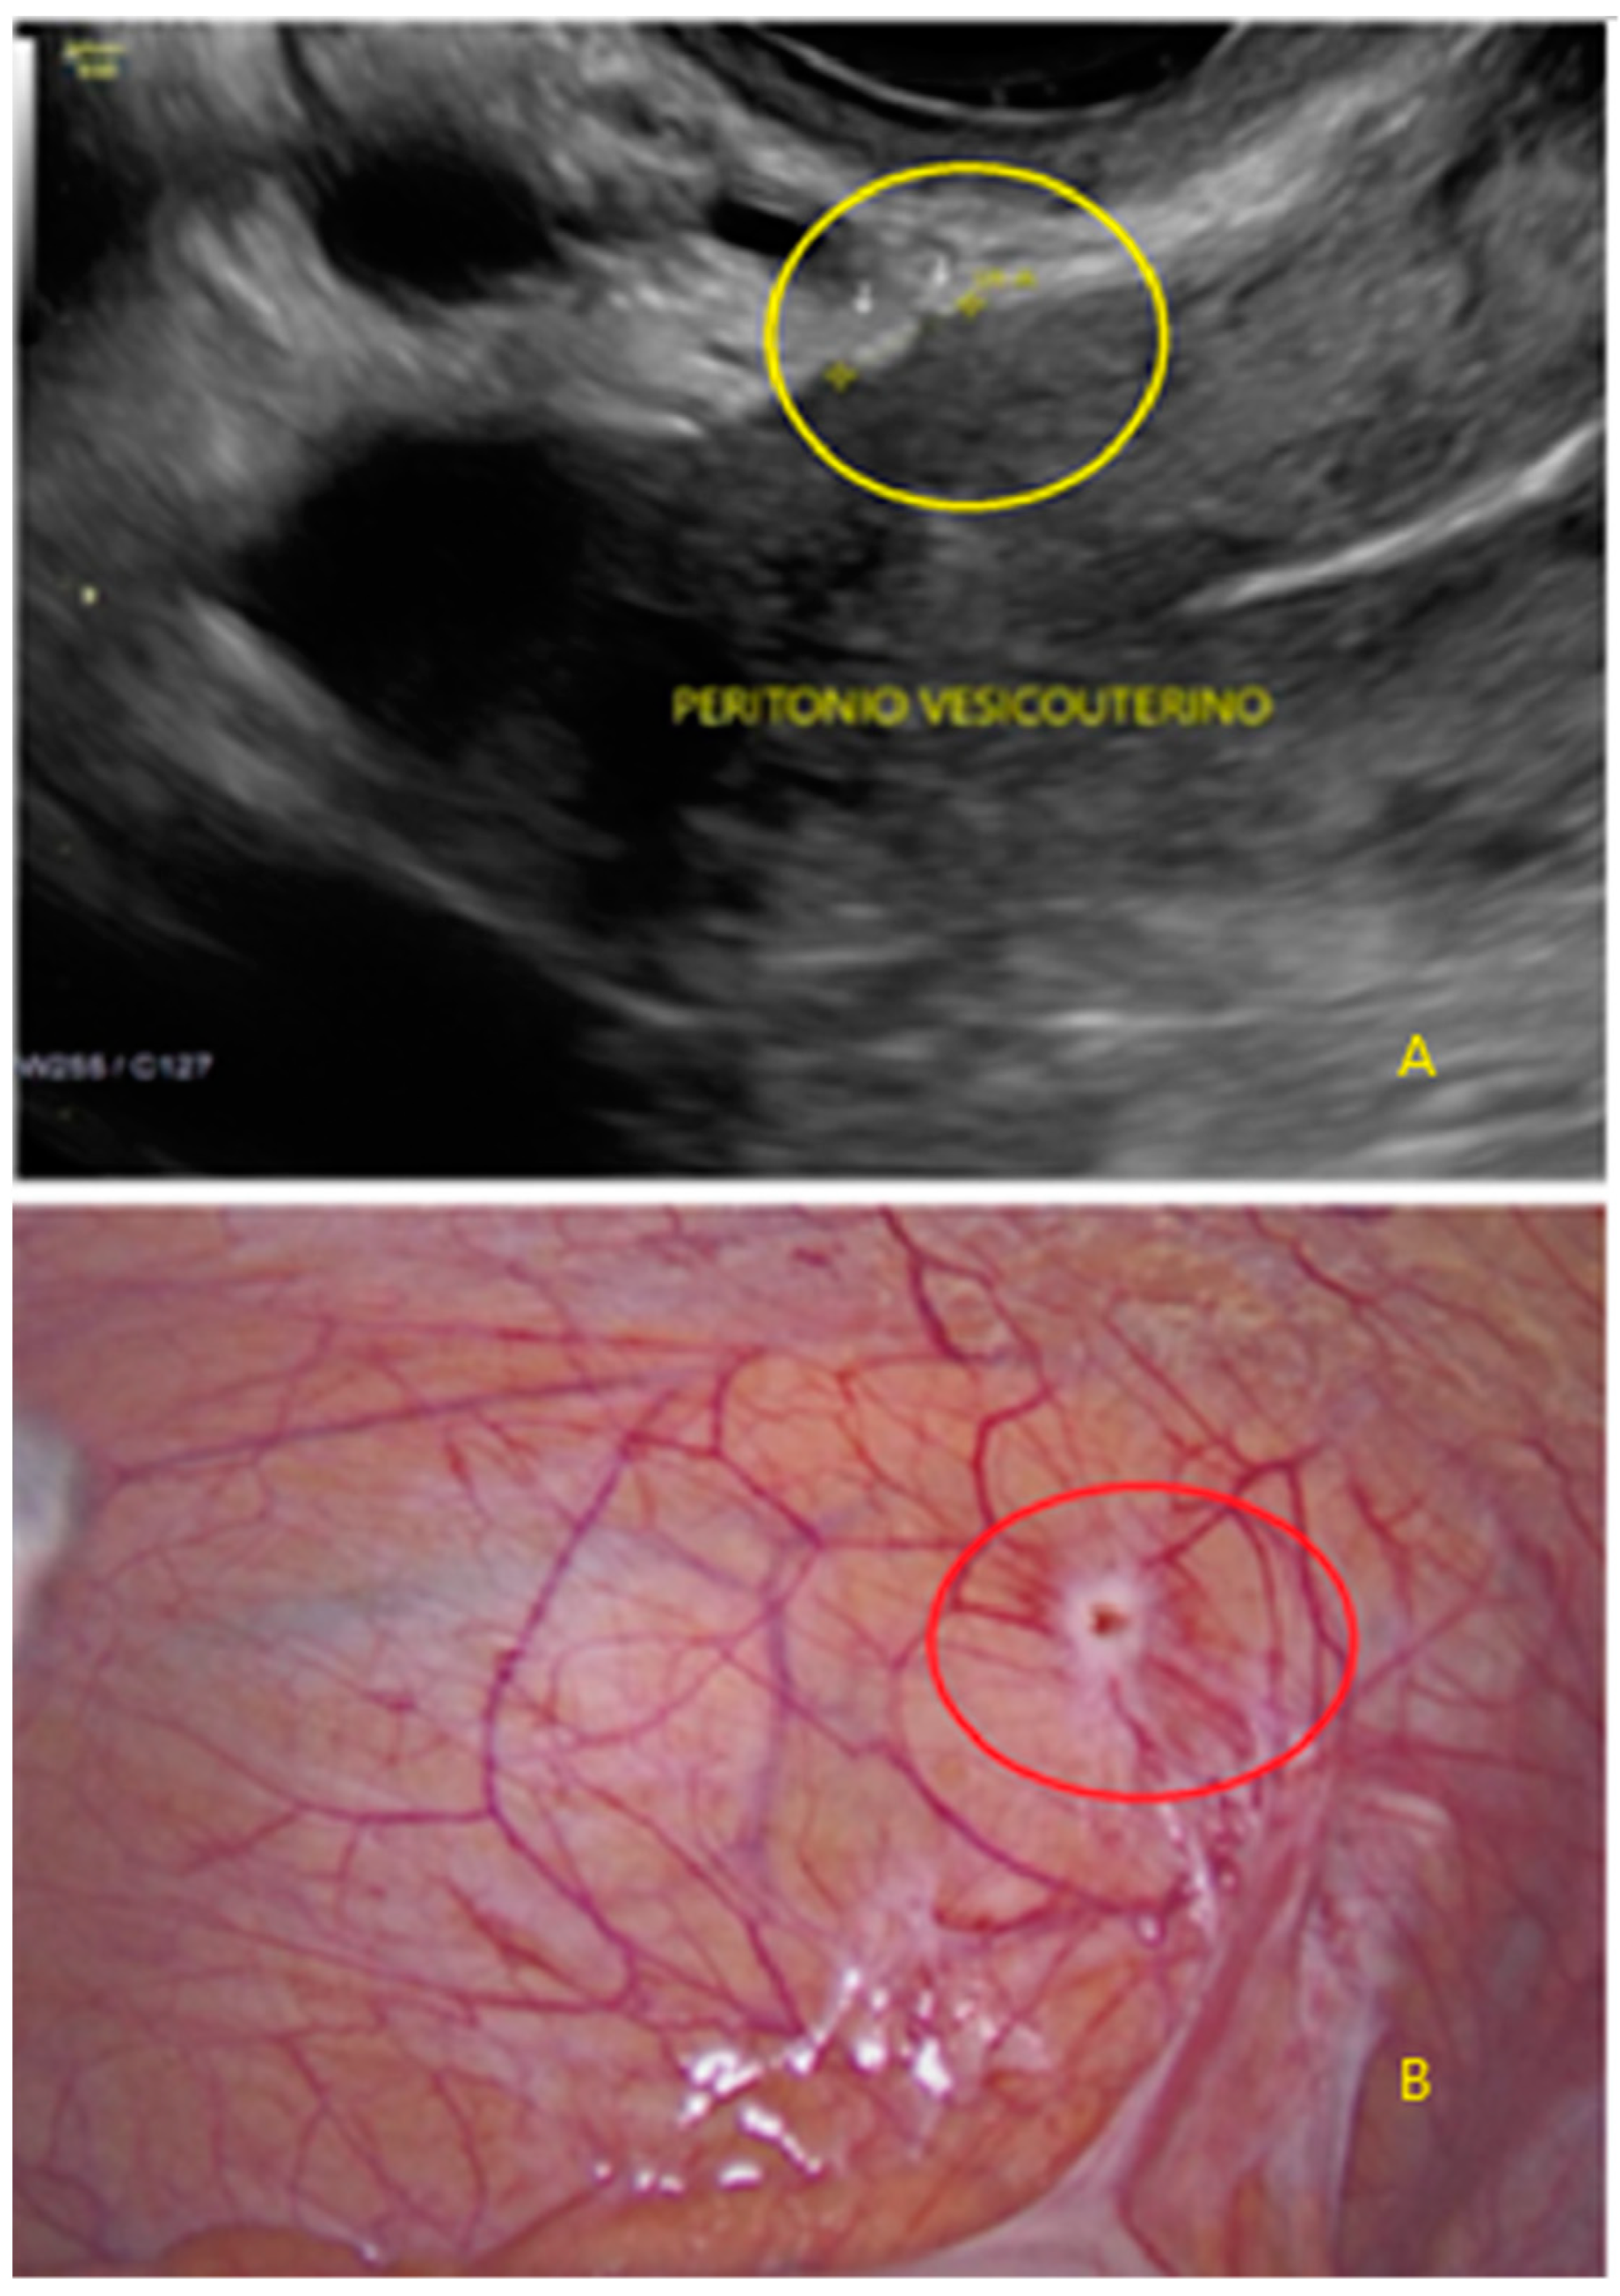

- The lesion may be convex, protruding from the peritoneal surface into the peritoneal cavity (we called this “bulging”), or it may appear as a concave defect in the peritoneum (we called this a “pocket”).

- The presence of hyperechoic foci (we called this a “pearl”).

- The presence of velamentous (filmy) adhesions associated to the lesion (we called this a “veil”).